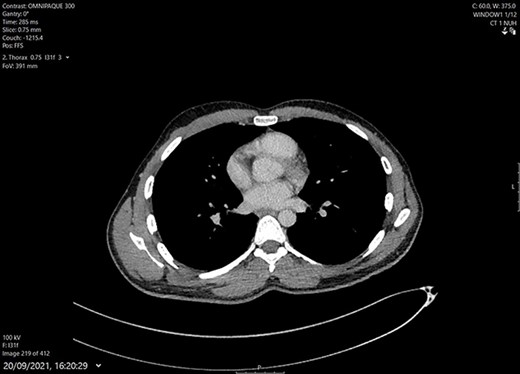

A 31-year-old healthy south-east Asian male presented as a general surgical emergency to a tertiary care facility with a 3-month history of a mass on the right side of his chest. It had progressively increased in size and become painful and erythematous days prior to his presentation. He reported no fevers, shortness of breath, cough, night sweats or weight loss. On examination, it was thought to be a suppurative chest wall abscess (Fig. 1). His inflammatory markers on admission bloods were within normal range. His chest X-ray showed, ‘linear and nodular densities in the right upper zone suggestive of an acute inflammatory process and a new ill-defined density overlying the right lower zone’ (Fig. 2A). Due to concerns of the abscess fungating into the breast or chest wall, he had a computerized tomography (CT) scan of his thorax with contrast. This showed a ‘10 × 4.5-cm mass with internal septations and surrounding fat stranding, arising from the anterior chest wall, with no bony destruction of the fifth anterior rib (Fig. 2B). There were signs of old TB within the lungs with tree-in-bud changes within the right apex suggestive of an acute on chronic infection’.

(A) Chest X-ray: linear nodular density right upper lobe. (B) CT Thorax at presentation showing the right-sided anterior chest wall, septating mass highly suspicious of a TB infection.